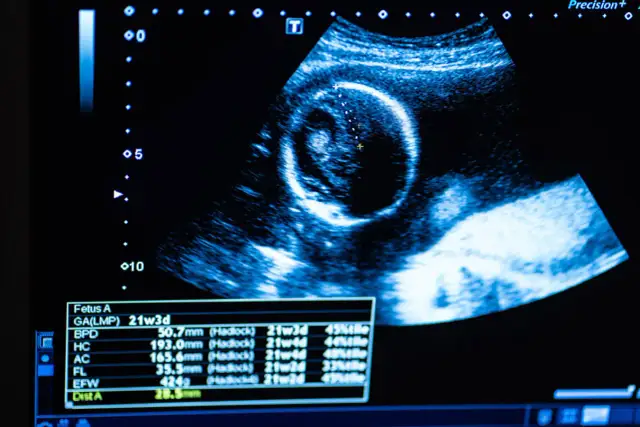

BadaniaUSG w ciąży: Bezpieczny przewodnik po badaniach i rozwoju dzieckaEwa Chmielewska-18 września 2025